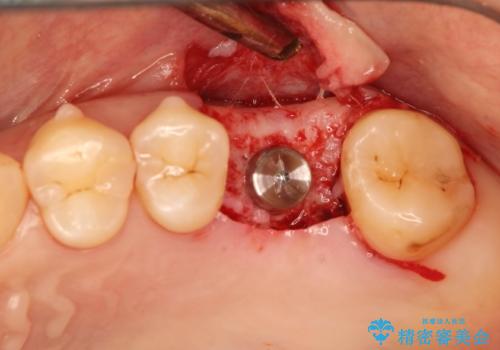

- 歯根破折を生じた奥歯を抜歯後、治癒の期間を経てインプラントを埋入

→2時手術の後、インプラントレベルの型どりにて上部構造まで完成させる

インプラントの種類:Zimmer spline